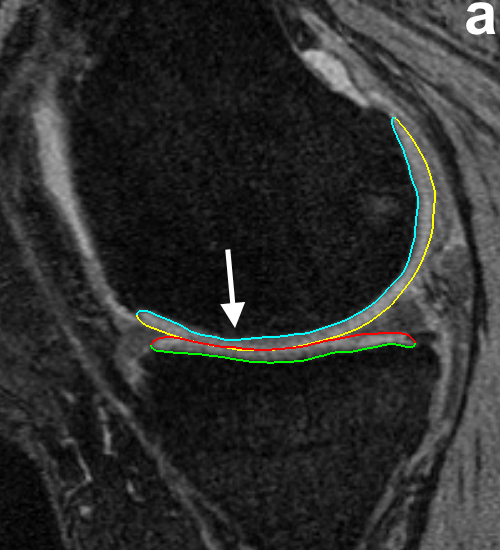

For analysis of the cartilage structures, accurate segmentation is a crucial first step. In clinical research there is a need for reproducible fully or highly automated segmentation as it offers consistent accuracy and speed over manual segmentation efforts. However, automated knee segmentation is challenging due to the thinning cartilage, appearance of osteophytes, bone marrow and cartilage lesions and surface fibrillation in MRI data. Several of these disease artifacts appear similar to the cartilage further increasing the segmentation complexity (Fig. 8a).

RF classifiers [34] were used to provide better and location-specific cost functions. RF classifiers use the concept of bagging, where for each decision tree a random subset of features is chosen thereby reducing inter-decision-tree correlation, which improves accuracy. A single RF classifier was used in [30] where the limitation was that all the information used was localized along the graph columns. Because of this locality, features were unable to capture information of the neighborhood that appeared larger than a few nodes along the column. There are several anatomical features that appear locally like a cartilage boundary but when examined in a global neighborhood may be combined with pathology (e.g., synovial fluid, Fig. 8). Further, the single RF classifier did not account for the regionally-specific appearance of the surrounding menisci, muscle, bone and other anatomies. As a result, certain intensity profiles appearing in a specific normal-cartilage region of the knee also occurred in another local region in a pathological case. This discrepancy resulted in the improper training of the classifier and contributed to segmentation inaccuracy.

Fig. 8 qualitatively shows the improvement of 4D LOGISMOS over 3D. Note the lack of an obvious edge distinguishing the tibia and femur cartilage. Using the spatial and temporal contextual information from all the time-points, the 4D method is able to correctly position the cartilage for the tibia and femur despite the lack of image information locally.